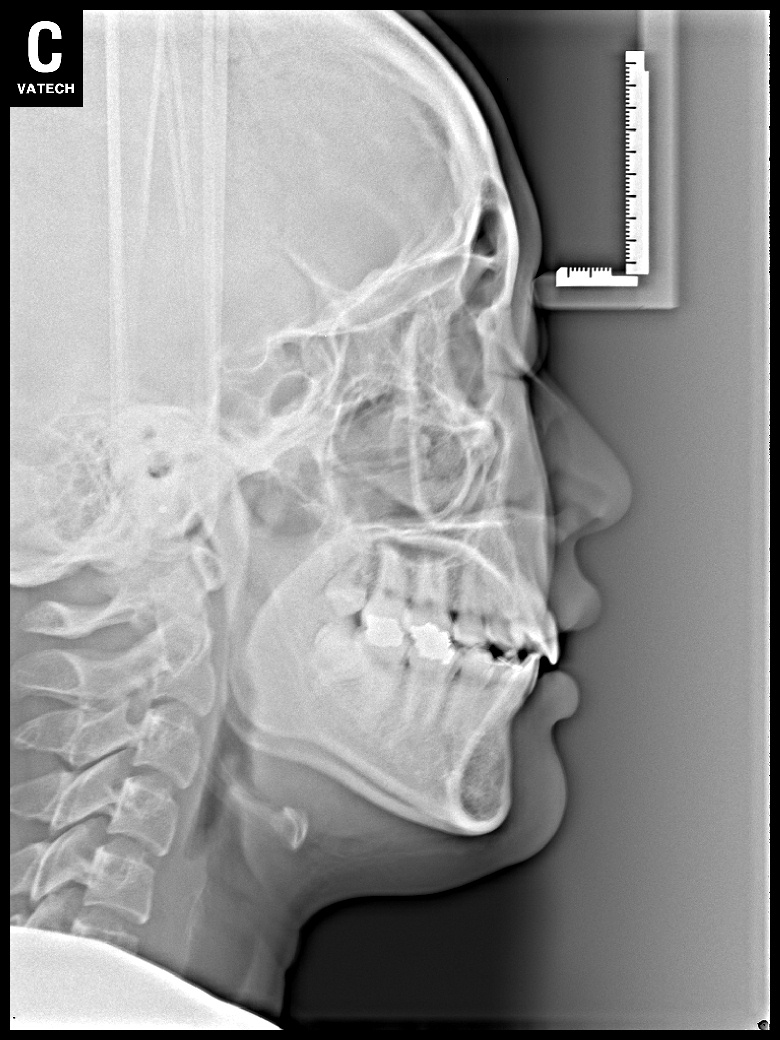

치료 후 사진입니다.